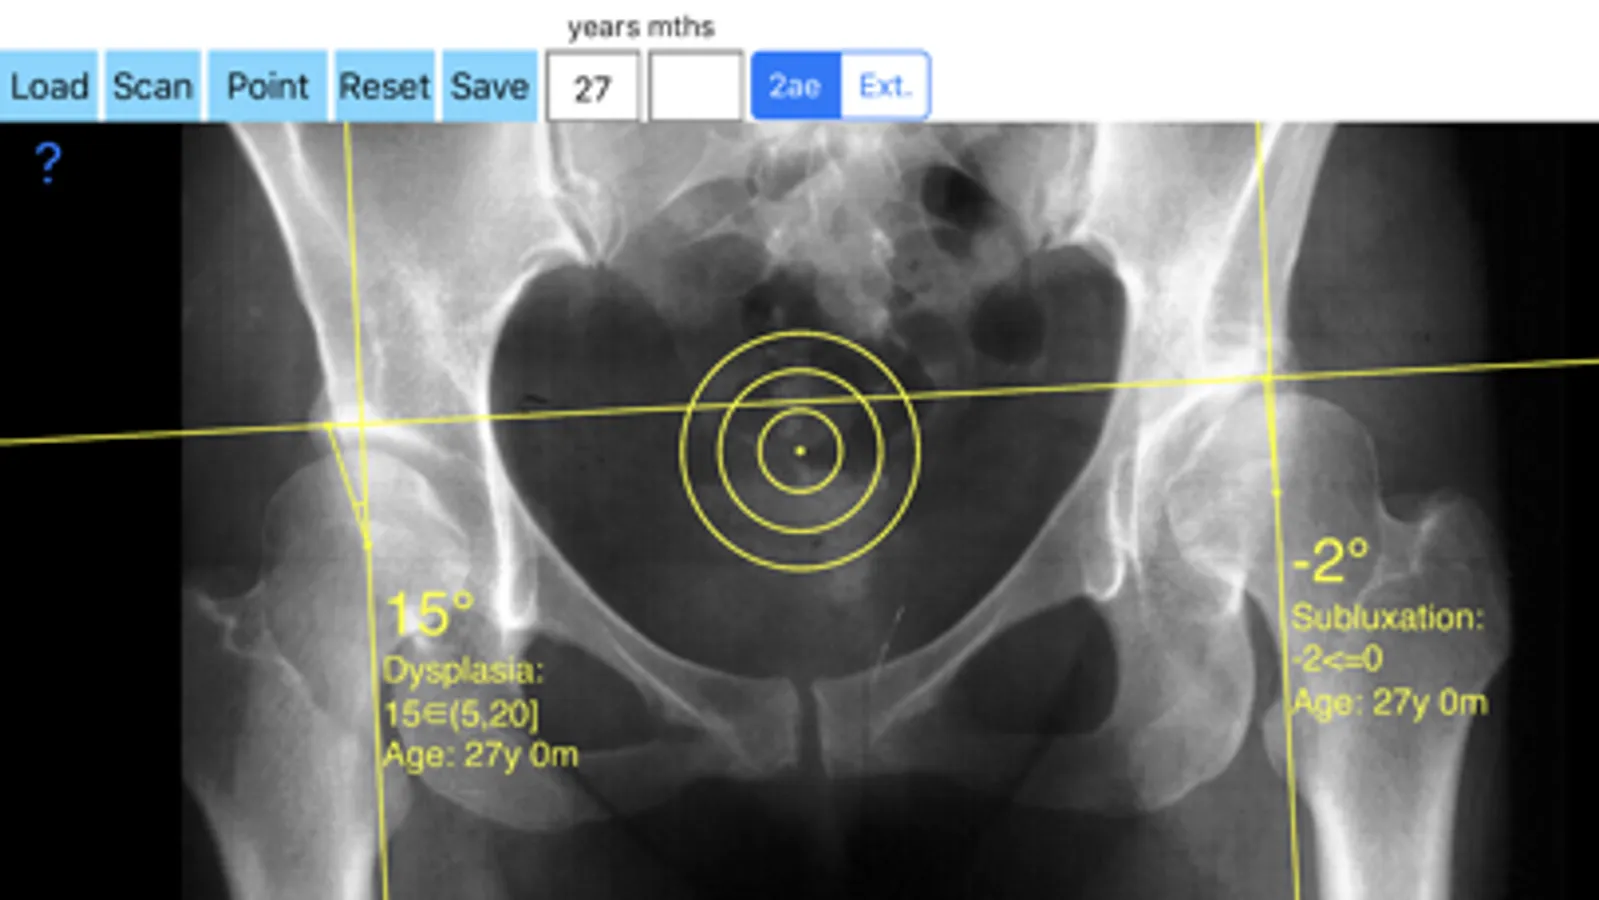

-Securely import medical images directly from the camera or stored photos

-Offers a very convenient way to determine the most accurate possibly lines in order to measure the angles. By the aid of a circular transparent template, the points of interest are marked accurately. The automatically formed lines, drawn between points, measure automatically the angles of interest. The results are printed in degrees. By inputting the age, the measured angle is compared with values from normal reference database. In case the measured angle is beyond the normal range for that age, the hips are categorized as normal, borderline dysplastic, dysplastic or severe dysplastic or over coveraged, pincer type femuracetabular impingement (FAI) of the hip.

The app is a handy tool for an orthopaedic surgeon, radiologist, medical student or resident who wants objectively to monitor and determine the severity of dysplasia of the hip. The build-in comparison feature with the normal reference values according to patient age may help decide what could be considered normal or dysplastic or pincer (FAI). The app is not a simple goniometer, is an enhanced product which offers the ability to compare all the input data with medical reference database. The results are printed on the screen and the hips are categorized as normal or dysplastic or severe dysplastic or pincer (FAI) according to the angle measured. This feature it is particular useful especially in clinical settings where you need a quick results without losing time in looking for reference data according to age variations in huge textbook. The circular template to determine the points of interest and to mark them accurately are very useful in clinical settings where finding a sharpened pencil, a protractor and manage to draw with ruler lines over the patients x-rays is definitely a cumbersome and tedious task. You can load from your photo library or capture a photo from x-rays of the patient in you mobile phone or tablet, the App simply guides you to do the rest.